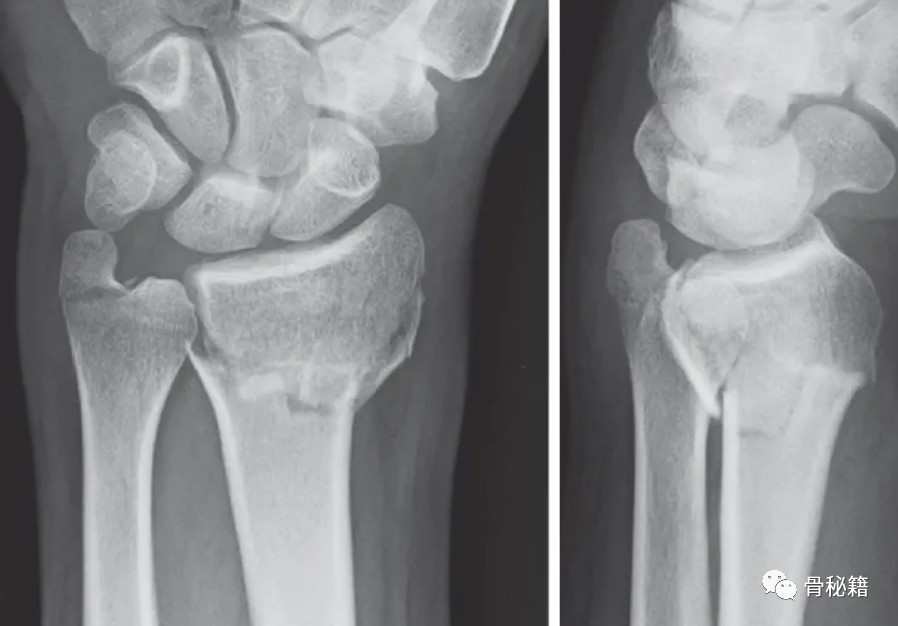

尺骨茎突基部骨折使 DRUJ 的稳定性受到质疑

采用茎突入路进行手术复位与固定